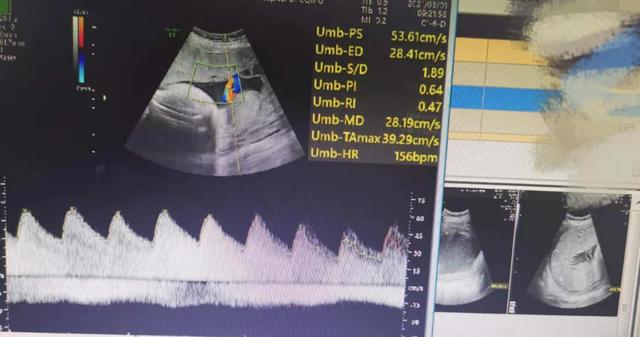

超声检查提示:胎先露:头。NuA:0。胎盘位置:宫体前壁及右侧壁。成熟度:3级。胎盘厚度 40mm,下缘距宫颈内口显示不清。羊水深度44.31.36.39mm。胎心、胎动有。脐动脉S/D1.78,PI:0.58。胎心率150pbn,律齐。